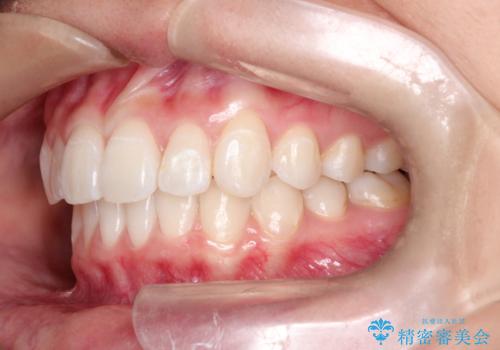

前歯の突出、深い噛み合わせ、ガタつきをマウスピース矯正(インビザライン)で治療した症例

- 初診時には上顎前歯の突出、前歯部の深いかみ合わせ、叢生が見られる状態でした。

このケースでは非抜歯にて奥歯を後方に移動させる事で前歯の突出を改善するスペースを作り出していますが、これはマウスピースと顎間ゴムの併用によるもので、患者様のご協力の賜物と言えます。

深い噛み合わせについてはシミュレーション上の結果と、予期される実際の歯の移動量とを考慮し、特殊なセットアップを行う事で望ましい結果を得ることができました。

治療途中でリファインメントという追加のマウスピースを製作する手順を行っていますが、その際に上下の正中を合わせたいとの要望があったため、追加シミュレーションの際に追加でセットアップを施しましたが、無事、上下の正中もご要望通りに改善しています。